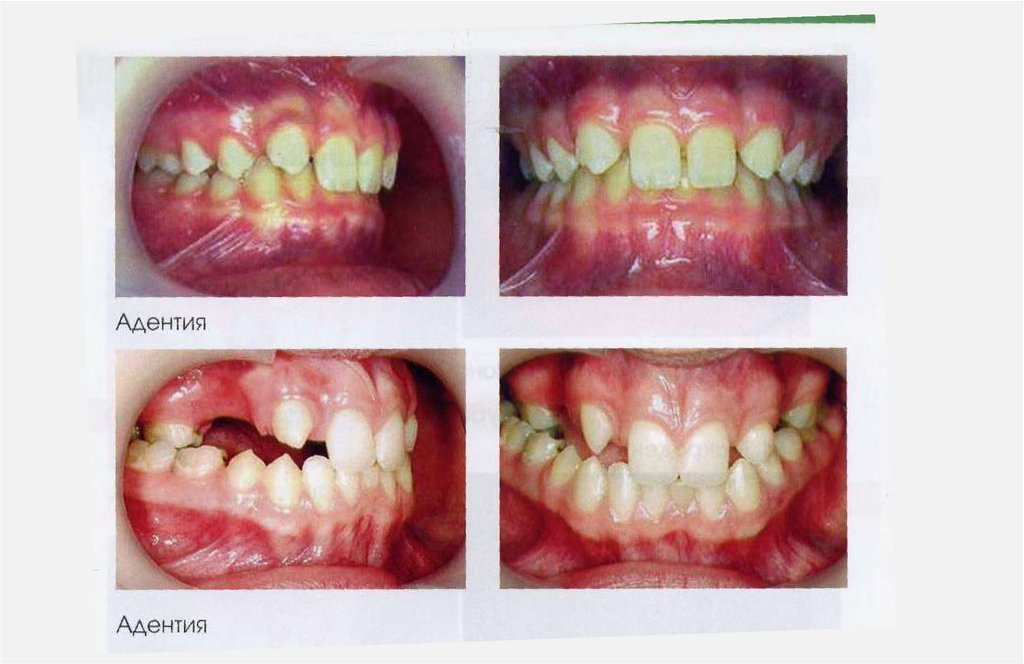

1. АНОМАЛИИ ЗУБОВ

1.1. Аномалии формы зуба

1.2. Аномалии структуры твердых тканей зуба

1.3. Аномалии цвета зуба

1.4. Аномалии размера зуба (высоты, ширины, толщины) (1.4.1. макродентия, 1.4.2.

микродентия)

1.5.Аномалии количества зубов ( 1.5.1. Гиперодонтия, 1.5.2. Гиподонтия)

1.6.Аномалии прорезывания зубов ( 1.6.1. Раннее прорезывание, 1.6.2. Ретенция)

1.7.Аномалии положения зубов (в одном, двух, трех направлениях) (1.7.1. Вестибулярное,

1.7.2. Оральное, 1.7.3. Мезиальное, 1.7.4. Дистальное, 1.7.5. Супраположение, 1.7.6.

Инфраположение, 1.7.7. Поворот по оси (тортоаномалия), 1.7.8. Транспозиция)